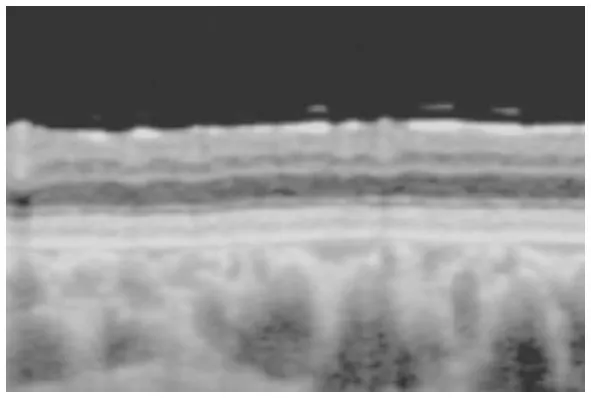

Horizontal images of OCT of the macula (A, Patient 4-2; and B, Patient 6-1 in Table 1). Cystoid changes in the GCL (arrows) are much fewer than those in the INL. Arrowheads: cystoid changes in the outer segment of the photoreceptors.

In the periphery, OCT revealed that bullous retinoschisis was a result of splitting in the GCL, although many cystoid changes or intraretinal schisis were observed in the INL at the posterior edge of the retinal splitting (Figures 1C, 2B,C). In Patient 2-1, horizontal scanning superior to the fovea revealed intraretinal cystoid changes in ONL, INL, and GCL, but no changes were observed in the retinal nerve fiber layer (Figure 2D). The cystoid changes in the GCL were frequently observed in the periphery but rarely found in the macula (Figures 2C, 3B,C, and 4).

This study reported detailed ultra wide-field OCT findings in the peripheral retina of patients with XLRS. OCT revealed that split and/or cystoid changes in the INL were common to both the macula and peripheral retina. However, cystoid changes in the GCL were observed in the peripheral retina, but rarely in the macula (Figures 2–4). Peripheral retinoschisis resulted from splitting of the GCL (Figures 1C, 2C).